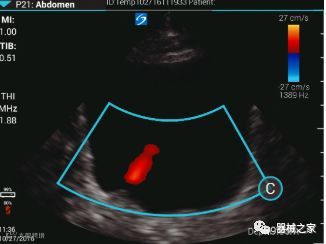

在几年前,超声波无法对小型慢流血管中的血流进行成像,但现在有少数供应商提供具有此功能的系统。该特征提供了另外一种检查病变以指示癌症或炎症的方法。其中一个是佳能Aplio 900 CV系统,它可以显示毛细血管中的血流量。日立的Arietta 65中程系统提供了一种可视化小血管的功能,可以更好地观察肾脏等器官的灌注情况。三星RS85还提供MV-Flow可视化慢流微血管结构。